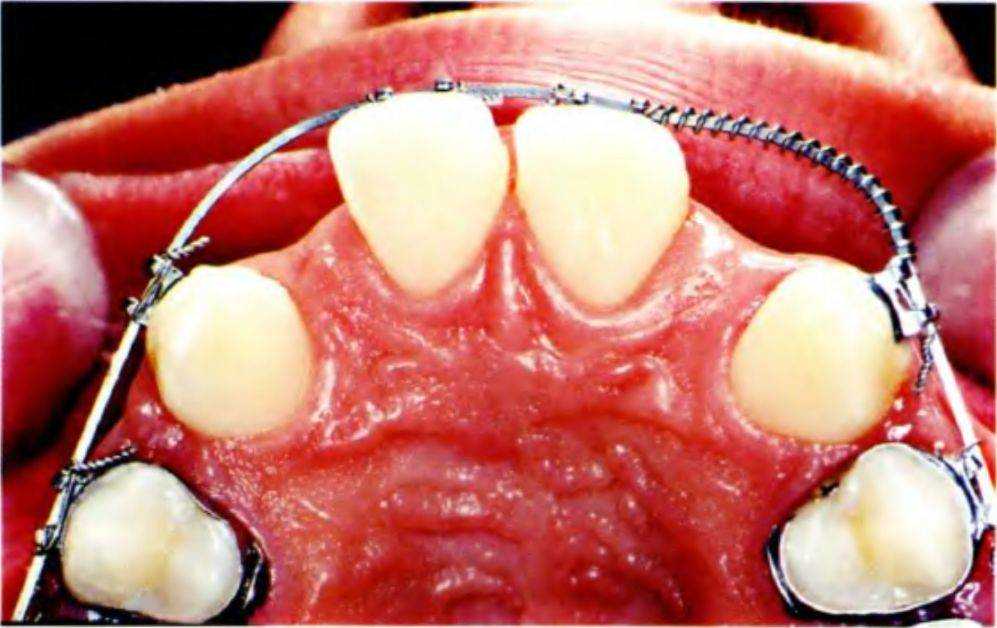

Рис. 5-Зе. Увеличенные пространства (небный вид)

Планируется перемещение зубов латерально для создания пространства для установки имплантатов и последующего протезирования (рис. с 5-За по 5-Зе).